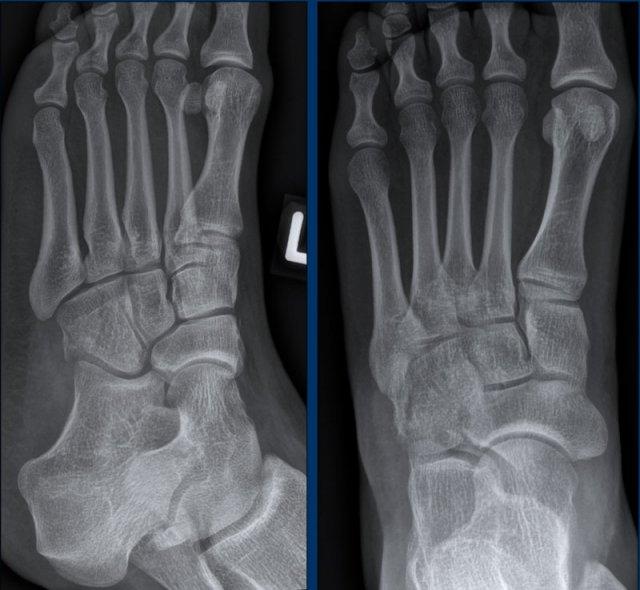

Ca 3 – Chấn thương bàn chân

Hình ảnh cho thấy những dấu hiệu gì và có ý nghĩa như thế nào?

Nhấp vào hình ảnh để xem phóng to.

Ca 4 – Chấn thương bàn chân